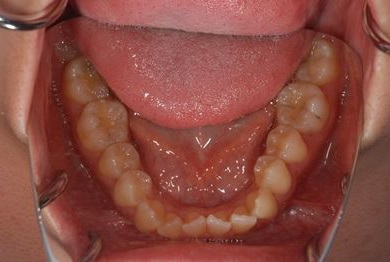

治療後

• 治療後